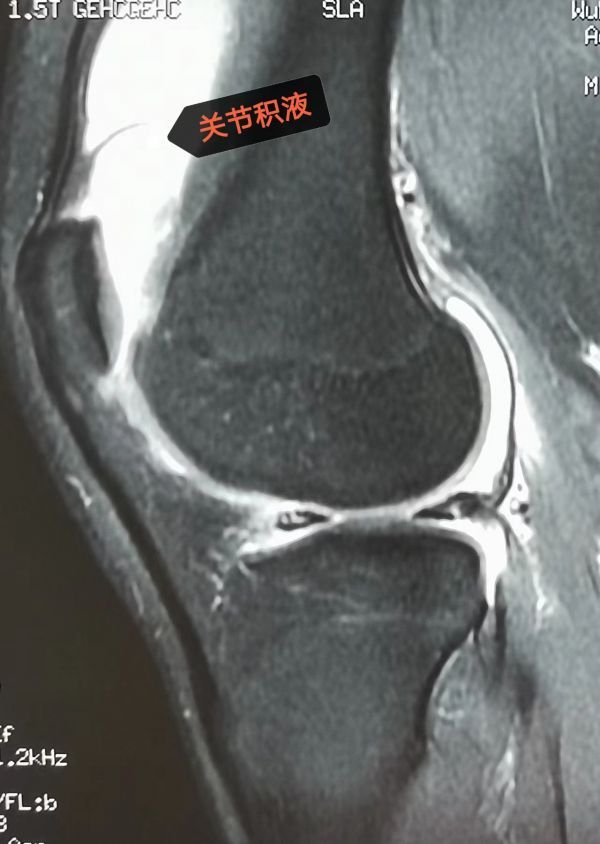

关节积液区域。